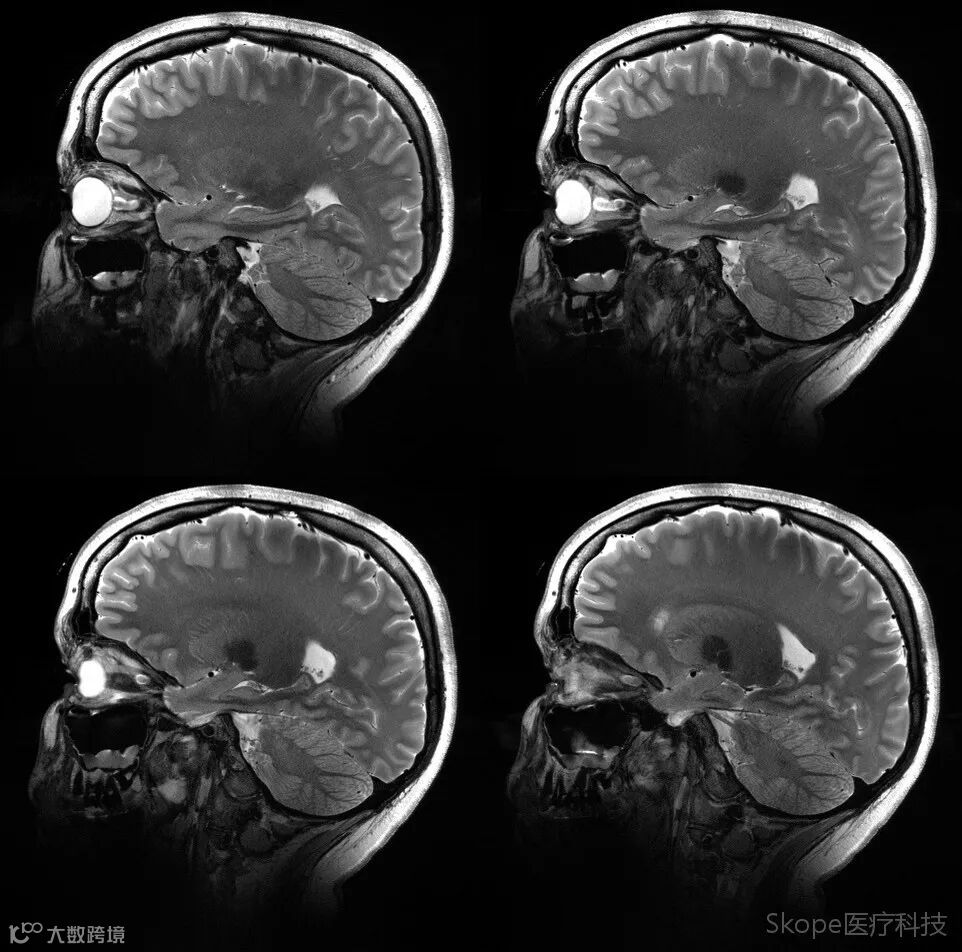

Axial T2 Turbo Spin Echo

左右颞叶信号均匀性良好,且深部脑结构具有良好的信噪比,三叉神经清晰可见。

Sagittal T2 TSE

pTx有效改善了小脑区域图像均匀性。

Right brain hemisphere

Left brain hemisphere

Axial T2 TSE